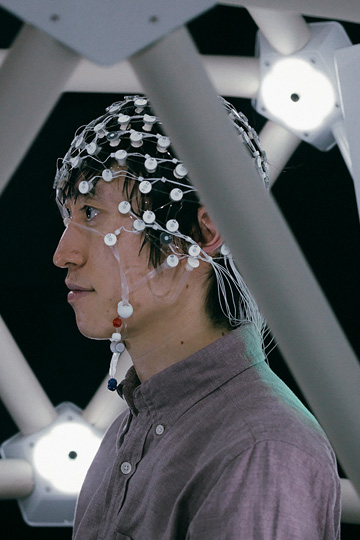

脳と機械を接続して身体運動を補助するBMI技術の基礎研究から応用研究、医療機器開発まで、一気通貫で取り組んでいます。

SCIENCE

TECHNOLOGY

APPLICATION

DESIGN